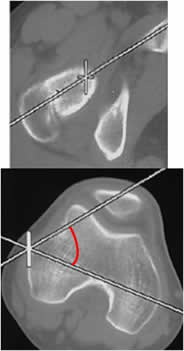

La medición ideal se realiza con TAC y valora la rotación entre el cuello femoral y los cóndilos femorales. Se mide mediante cortes axiales, que se superponen. Uno sobre el eje del cuello femoral y otro que une la parte posterior de los cóndilos femorales.

(3, 18). (Fig 59, 60 A y B).

Fig 59. Anteversión femoral.

A: TAC axial sobre el cuello femoral, con línea discontinua sobre su eje.

B: TAC axial a nivel de la rodilla. Línea que une la parte posterior de los cóndilos femorales y al superponerla, forma el ángulo de anteversión.